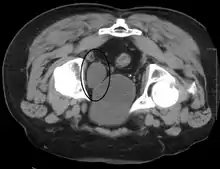

Investigations performed usually include collecting a sample of urine for an inspection for malignant cells under a microscope, called cytology, as well as medical imaging by a CT urogram or ultrasound.[27] If a concerning lesion is seen, a flexible camera may be inserted into the bladder, called cystoscopy, in order to view the lesion and take a biopsy, and a CT scan will be performed of other body parts (a CT scan of the chest, abdomen and pelvis) to look for additional metastatic lesions.[27]

Some forms of medical imaging exist to visualise the bladder. A bladder ultrasound may be conducted to view how much urine is within the bladder, indicating urinary retention. A urinary tract ultrasound, conducted by a more trained operator, may be conducted to view whether there are stones, tumours or sites of obstruction within the bladder and urinary tract. A CT scan may also be ordered.